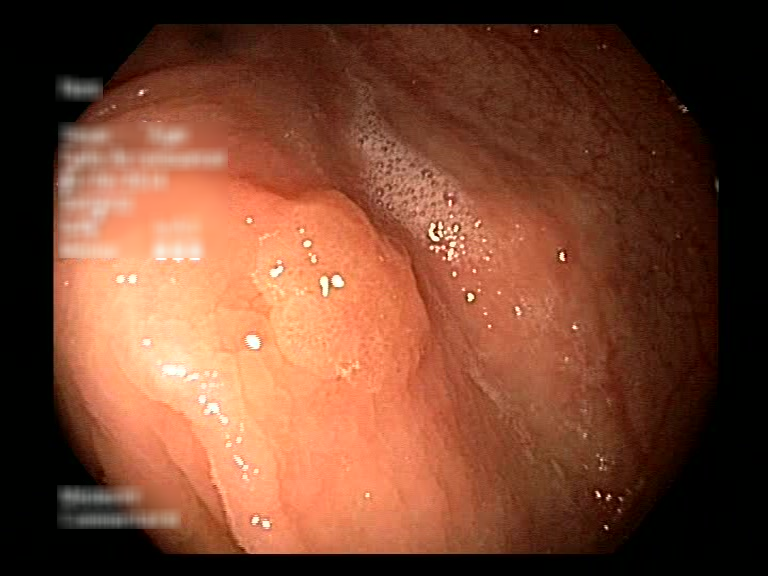

| Lesion | White Light Frame | NBI Frame | White Light Video | NBI Video | Camera Calibration |

| hyperplasic_01 |  |

|

WL.mp4 | NBI.mp4 | cam.xml |